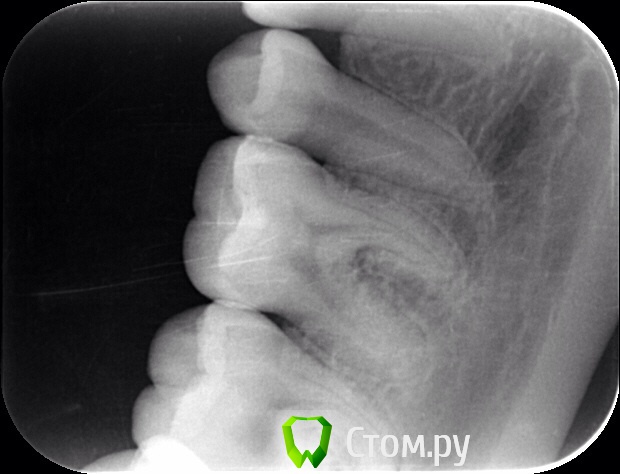

Naga Siren Опубликовано 20 октября, 2014 Автор Поделиться Опубликовано 20 октября, 2014 (изменено) Хорошо, спасибо, я тогда в лс напишу.Прилагаю еще фото Изменено 20 октября, 2014 пользователем Naga Siren Ссылка на комментарий